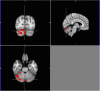

Expanding behavioral and neurobiological evidence affirms benefits of shared (especially parent-child) reading on cognitive development during early childhood. However, the majority of this evidence involves factors under caregiver control, the influence of those intrinsic to the child, such as interest or engagement in reading, largely indirect or unclear. The cerebellum is increasingly recognized as playing a "smoothing" role in higher-level cognitive processing and learning, via feedback loops with language, limbic and association cortices. We utilized functional MRI to explore the relationship between child engagement during a mother-child reading observation and neural activation and connectivity during a story listening task, in a sample of 4-year old girls. Children exhibiting greater interest and engagement in the narrative showed increased activation in right-sided cerebellar association areas during the task, and greater functional connectivity between this activation cluster and language and executive function areas. Our findings suggest a potential cerebellar "boost" mechanism responsive to child engagement level that may contribute to emergent literacy development during early childhood, and synergy between caregiver and child factors during story sharing.